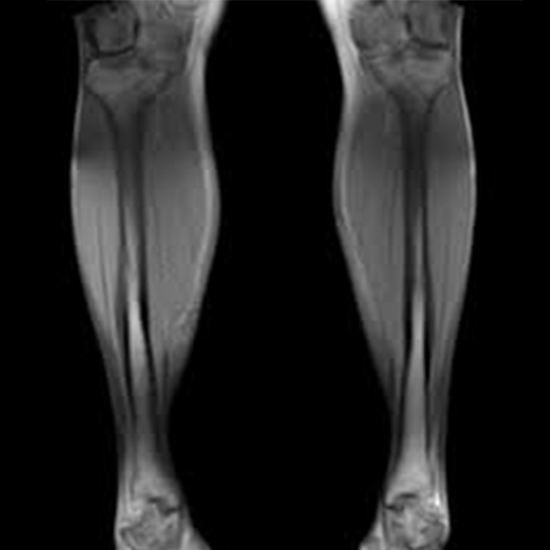

An MRI of the leg clearly shows the foot, ankle, knee, and leg. It shows bones, cartilage, and soft tissues like ligaments and tendons. An MRI can also show the meniscus, a cushion in the knee joint.